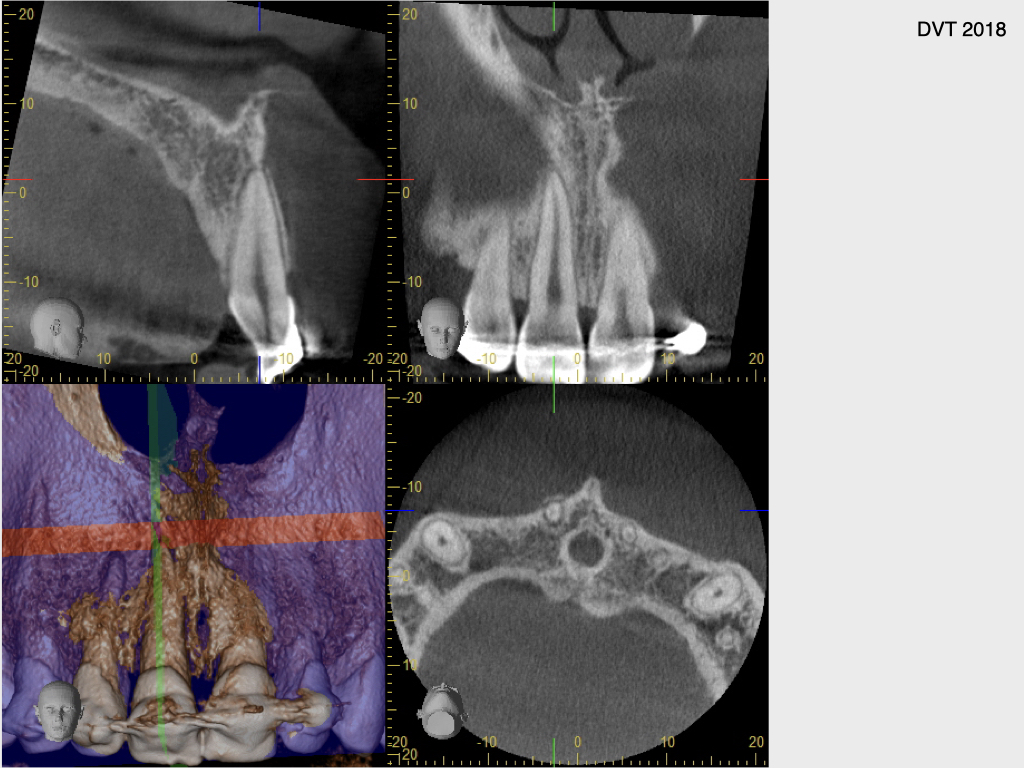

Z.n. Frontzahntrauma (1)